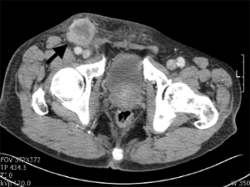

흉부 단순촬영(X-ray), 복부골반 전산화단층촬영(CT), 자기공명영상(MRI), 뼈동위원소검사(Bone scan)를 이용하게 됩니다. 국소 연부조직의 침윤과 림프절의 전이 여부는 전산화단층촬영(CT) 혹은 자기공명영상(MRI)을 통해 진단하고, 특히 요도암에 의한 음경 해면체의 침윤을 확인하는 데는 자기공명영상(MRI)가 유용합니다. 그 외 요도암의 국소 진행으로 직장의 침윤이 의심되는 경우에는 에스결장 내시경을 시행할 수 있습니다. 상부요로를 평가하기 위해서는 경정맥 신우조영술(IVP)을 시행합니다.

림프절 전이에 의한 우측 서혜부 림프절의 비대가 관찰됩니다.

[ 요도암 환자의 골반 컴퓨터 촬영 ]